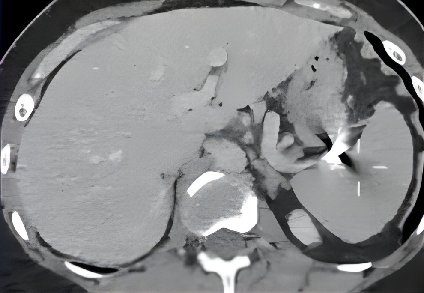

脾动脉远端动脉瘤栓塞 Hilar splenic aneurysm ~ 24 mm Coaxial catheterization / Rebar 18,Concerto detachable coils Coil packing density 28% Patent parent artery / Retained splenic perfusion Hilar splenic aneurysm Coaxial catheterization / R

Hilar splenic aneurysm |

Coaxial catheterization / Rebar 18,Concerto™ detachable coils |

Coil packing density 17% |

Patent parent artery / Retained splenic perfusion